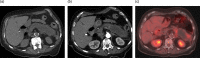

Intraductal papillary mucinous neoplasms (IPMN) of the pancreas have the potential for malignant progression into adenocarcinoma. Colloid or mucinous non-cystic carcinoma of the pancreas is an uncommon variant neoplasm that can arise within an intestinal type IPMN and have a relatively improved prognosis but may mimic the more lethal tubular or ductal adenocarcinoma. Colloid carcinoma is an infiltrating ductal epithelial neoplasm containing primarily extracellular stromal mucin pools and scant amount of centrally floating neoplastic cells. While several reports have evaluated the unique pathologic and immunohistochemical profile of colloid carcinomas, there has been limited radiologic-pathologic correlation in the literature. We report a case of an 83-year-old female who presented for evaluation of slowly progressive abdominal pain and was found to have colloid carcinoma arising from an IPMN. This is one of the first reports to correlate the multimodality radiology including cinematic rendering (CR) and histopathology features associated with this tumor. An enhanced understanding of the correlation between imaging appearance and specific histopathologic findings may aid in the early recognition and treatment of this rare neoplasm. Emphasis is placed on CR as this may help guide surgical management.